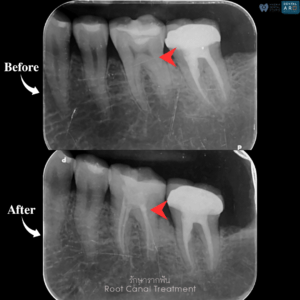

รักษารากฟัน

คือ การรักษาฟันที่เกิดการอักเสบและติดเชื้อภายในโพรงประสาทฟัน และเนื้อเยื่อรอบปลายรากฟัน อันมีสาเหตุมาการอักเสบและติดเชื้อภายในรากฟัน โดยทันตแพทย์จะทำการทำความสะอาดและใส่ยาในคลองรากฟัน และทำการอุดรากฟันเป็นขั้นตอนสุดท้าย การรักษารากฟันจะช่วยเก็บรักษาฟันให้สามารถคงอยู่ในช่องปากต่อได้ โดยไม่ต้องถอนฟันและไม่ต้องใส่ฟันทดแทน